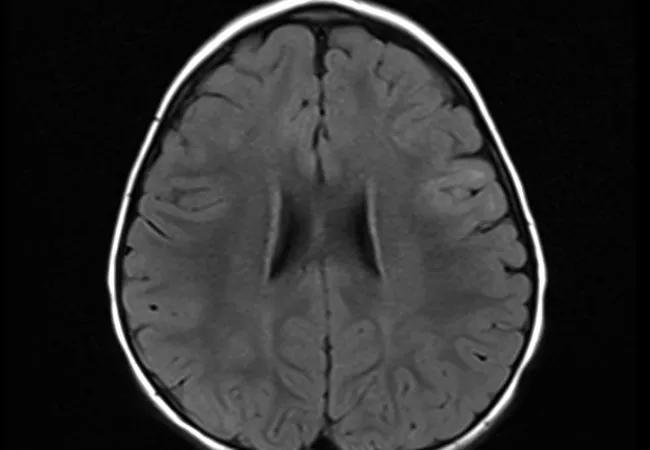

Continuous video EEG to rule out epilepsia partialis continua showed focal slowing on EEG. Brain MRI was significant for subtle FLAIR signal changes in the right frontoparietal region involving the precentral gyrus (Figure).

Figure. Axial FLAIR images demonstrating subtle hyperintensities in the left middle and inferior frontal gyrus.